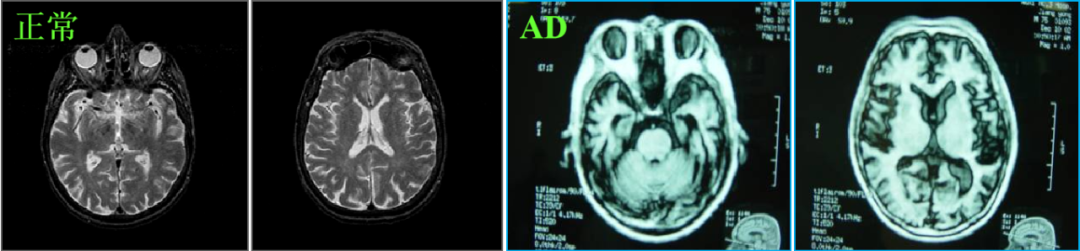

阿尔茨海默症(简称 AD)俗称老年痴呆这一疾病就像脑海里的橡皮擦会把记忆一点点抹去随着我国人口老龄化加速到2050年左右我国AD患者将超3000万人

当前,阿尔茨海默症的诊断主要靠两种检测方法,一种是脑脊液AD标志物检测,另一种是通过PET扫描仪的脑成像检测。在2018版的权威指南里,已将这两种检测作为诊断阿尔茨海默病的“金标准”。